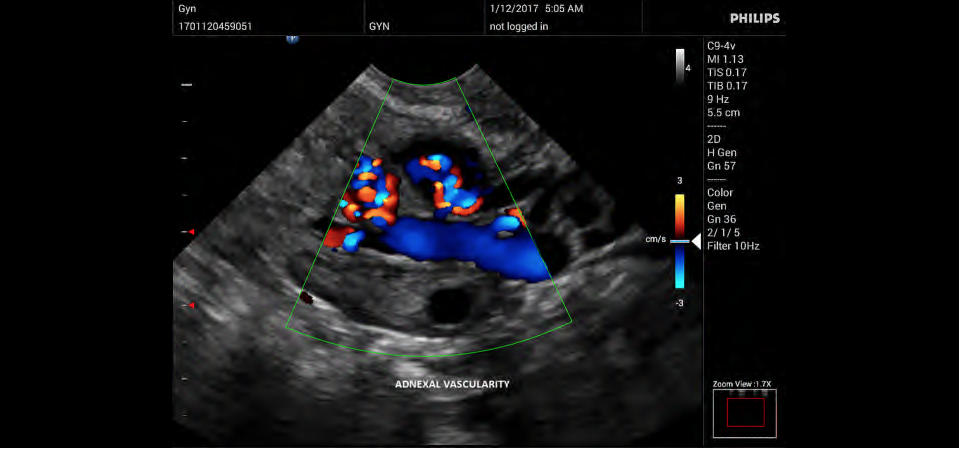

• Конвексный УЗИ датчик Philips C9-4v

• Цветное допплеровское картирование

• Направленный энергетический допплеровский режим: Дополнительно к возможностям визуализации сосудов в стандартном энергетическом режиме добавляется информация о направлении. Этот режим полезен для визуализации мелких сосудов в качестве замены цветного допплеровского картирования.

• Акушерство и гинекология;